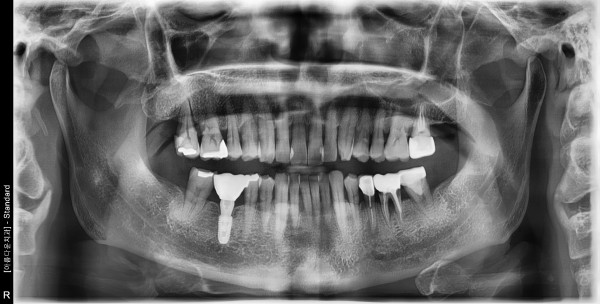

60세여자 왼쪽구치부 발치및뼈이식 임플란트식립